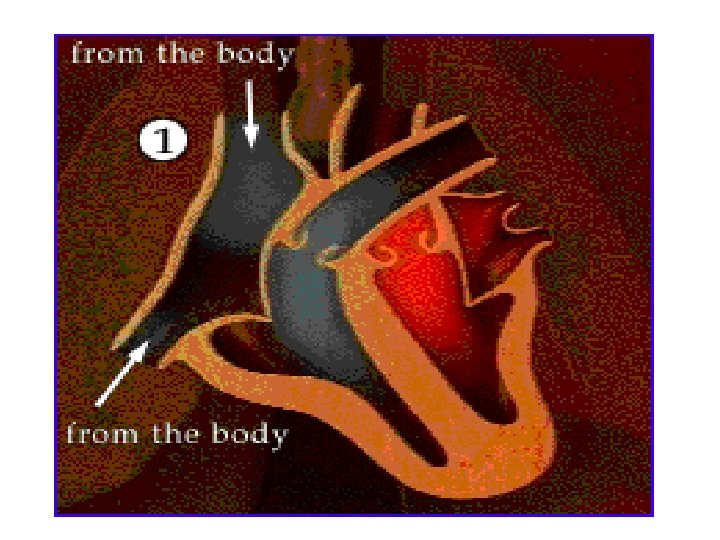

Internal Structure of the Heart • The heart has four chambers: the left and right atria (1 atrium) and the left and right ventricles. • The following diagram is the internal structure of the heart.

• Remember that the left side (RED) accepts and pumps out oxygenated blood. • The right side of the heart (BLUE) accepts and pumps out deoxygenated blood.

DEOXYGENATED BLOOD • This is blood that is depleted of oxygen because it has travelled around the body supplying the body cells with the oxygen. • The RIGHT side of the heart pumps deoxygenated blood which has a slightly blue colour.

Path of Deoxygenated blood • Vena cava right atrium • Through tricuspid valve right ventricle. • Ventricle contracts, tricuspid valve closes, semilunar valve opens. • Blood flows to the pulmonary artery lungs.